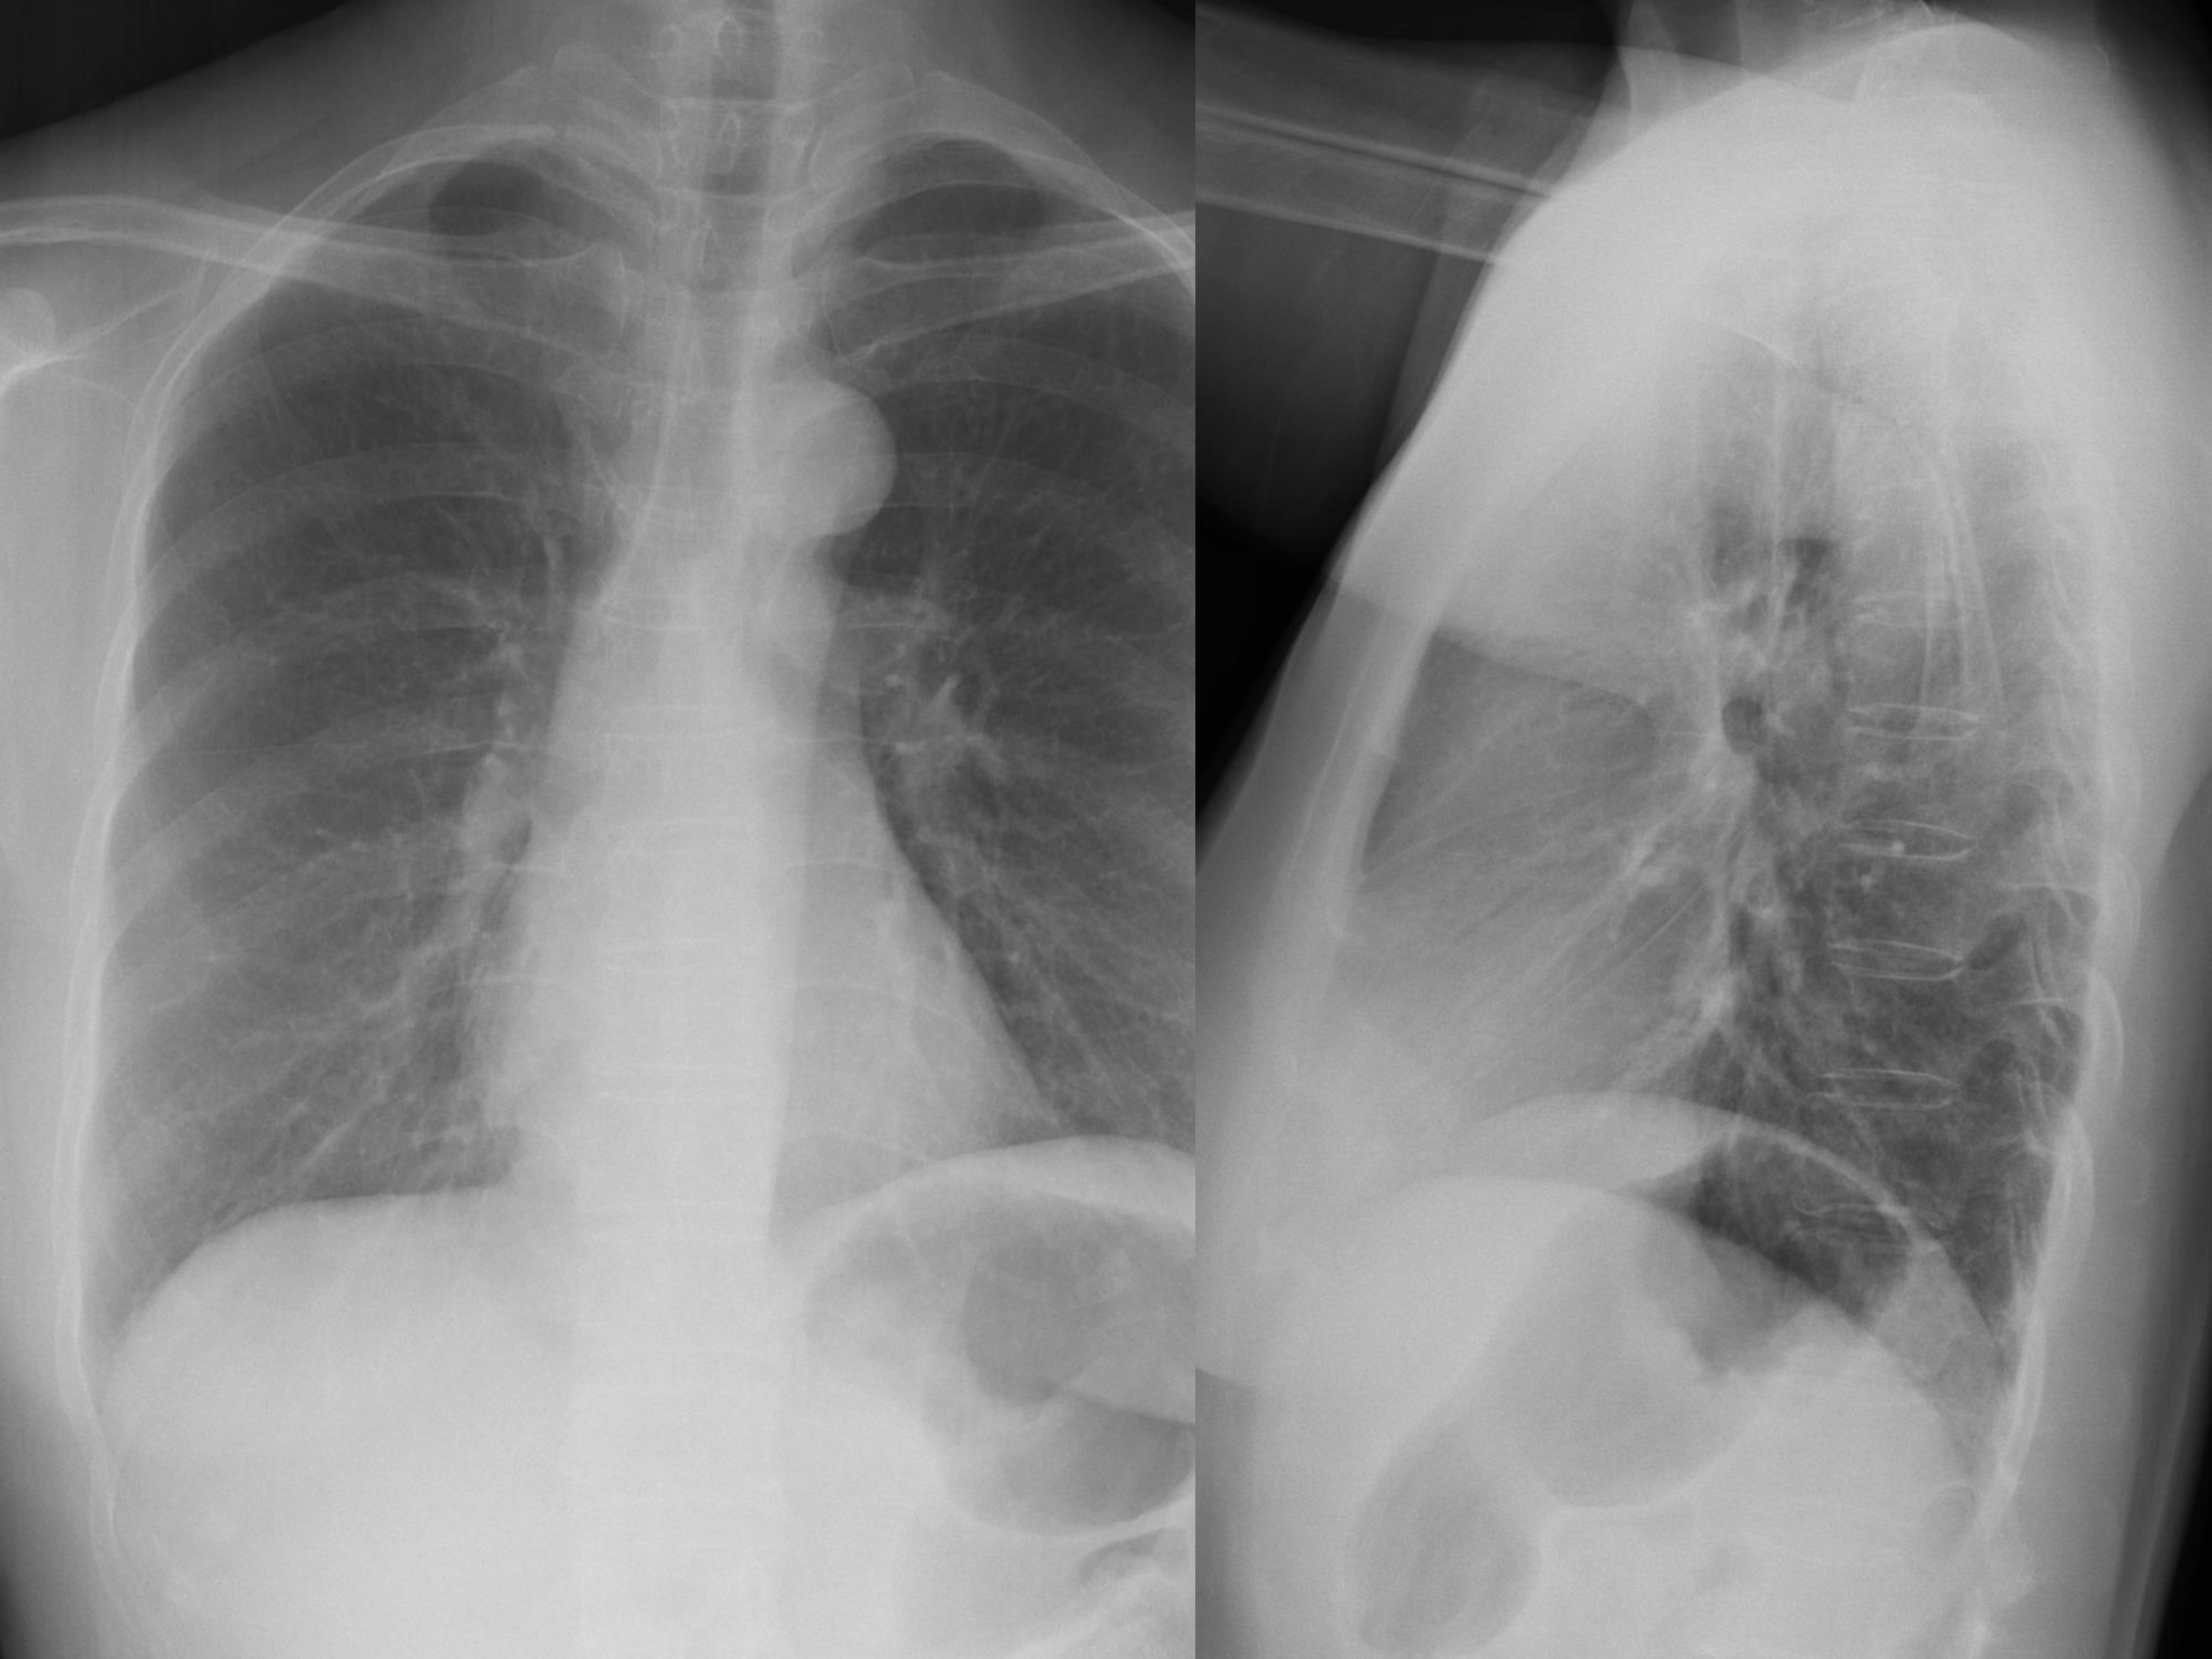

38a - Normal CXR prior to LTBI treatment.

38b - CXR one month after LTBI treatment shows a moderate right pleural effusion.

38d - CXR two months after MDR TB treatment show improvement.